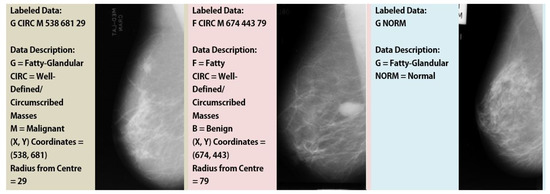

The digital mammography database from the MIAS, a consortium of UK research organizations, was utilized in this study as the dataset to evaluate the effectiveness of the proposed system [27]. This dataset was in the portable gray map (PGM) format, as shown in Figure 2. A 50 m pixel edge was applied to the digitized films. There were 1024 × 1024 versions of each image. The University of Essex’s Pilot European Image Processing Archive (PEIPA) provided access to mammogram images. The 322 left and right breast annotated photos in the MIAS dataset were divided into normal and pathologic lesions. Six categories, including calcification, architectural distortion, asymmetry, well-defined, spiculated, and ill-defined masses, were used to categorize the atypical samples. Additionally, each anomalous sample was accompanied by a description of its severity, such as normal, benign, or malignant, as depicted in Table 1, whereas the quantity of normal, benign, and malignant samples was not standardized. Therefore, we solely consistently distinguished between normal and abnormal classes.

Figure 2. Samples from MIAS Dataset (First two are examples of Abnormal and the last one belongs to the Normal Class).